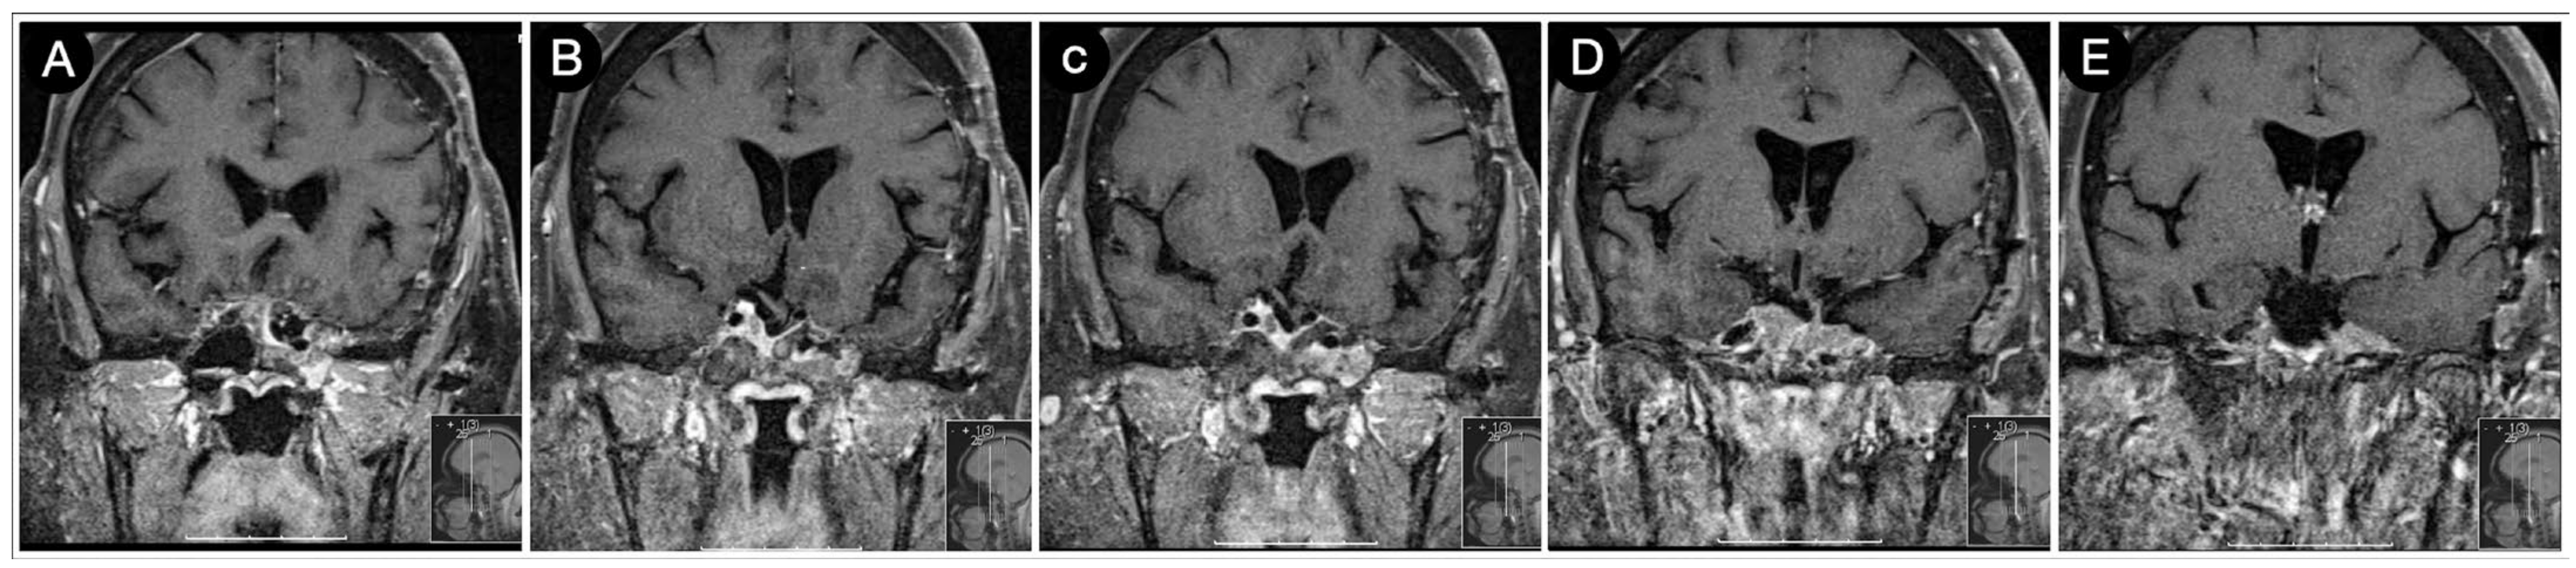

Case #1: Infradiaphragmantic Tumor with Middle Fossa Involvement through the Cavernous Sinus